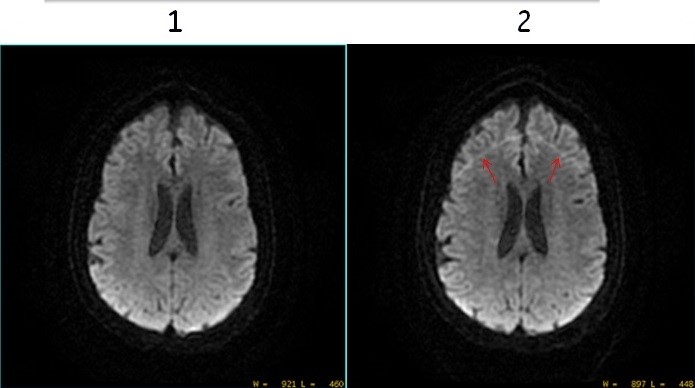

Figure 2. Classic turned on and off

Table 1. Image legend Number Description 1 DWI image with Classic Imaging Option selected (turned On). Note the improved image quality. 2 DWI image with Classic Imaging Option not selected (turned Off). Note the ghosting artifact due to incomplete fat suppression.